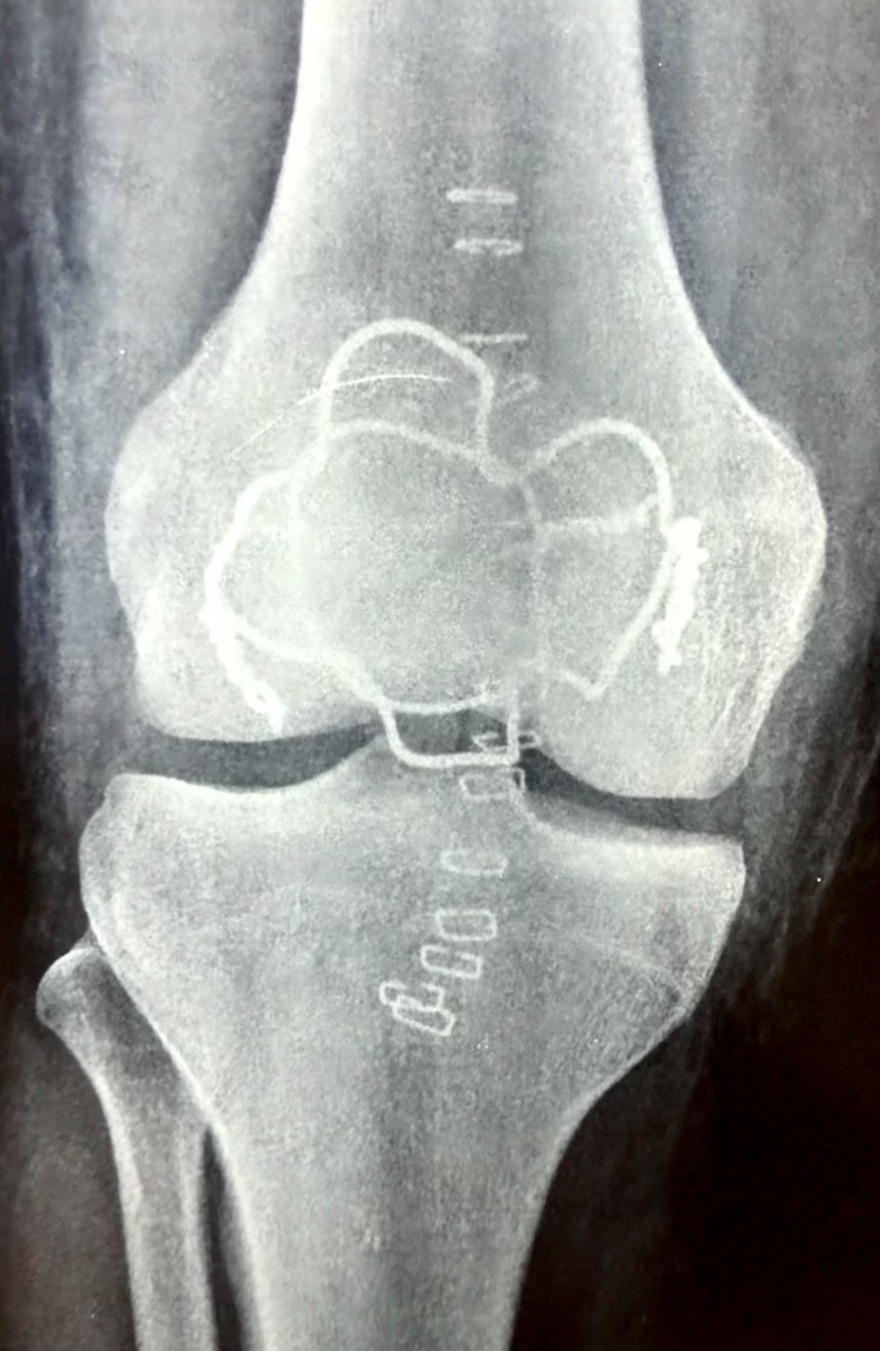

Δείτε ακτινογραφίες πριν την επέμβαση:

Τζάνειο νοσοκομείο: Νέα μέθοδος για την αντιμετώπιση συντριπτικών καταγμάτων της επιγονατίδας